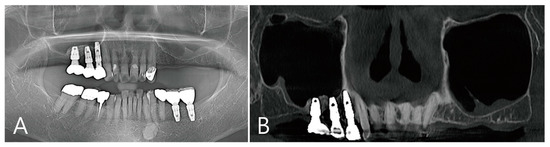

CBCT was taken immediately after MSA, one week after surgery, and before the uncovering procedure (Figure 3A–C). On the coronal image of the CBCT taken immediately after surgery, it was confirmed that MSA and implant placement were performed at the same time, and no dislocation of the bone graft particles was observed (Figure 3A). On the coronal image of the CBCT taken one week after surgery, severe grafting voids occurred on the upper part of the implant apex, and the maxillary sinus membrane was also thickened severely (Figure 3B). On the CBCT taken just before the uncovering procedure, the grafting void decreased in size, but a radiolucent image resembling SCC was observed. The thickened maxillary sinus mucosa was also reduced (Figure 3C). The grafting void was removed and a prosthesis was delivered. On the CBCT taken 6 months after the prosthesis was delivery, the radiopacity of the removed grafting void site was increased (Figure 3D).

Figure 3. (A) Coronal image of the CBCT taken immediately after surgery. There was no perforation of the maxillary sinus membrane and no leakage of the bone graft substitute; (B) coronal image of the CBCT taken one week after surgery. A severely enlarged grafting void was observed above the implant apex, and the ostium was obstructed due to severe membrane thickening; (C) coronal image of the CBCT taken 6 months after surgery. Although the grafting void was reduced in size, it appears similar to the SCC; (D) the radiopacity of the removed grafting void site was increased in the CBCT images taken 6 months after the prosthesis was delivered.